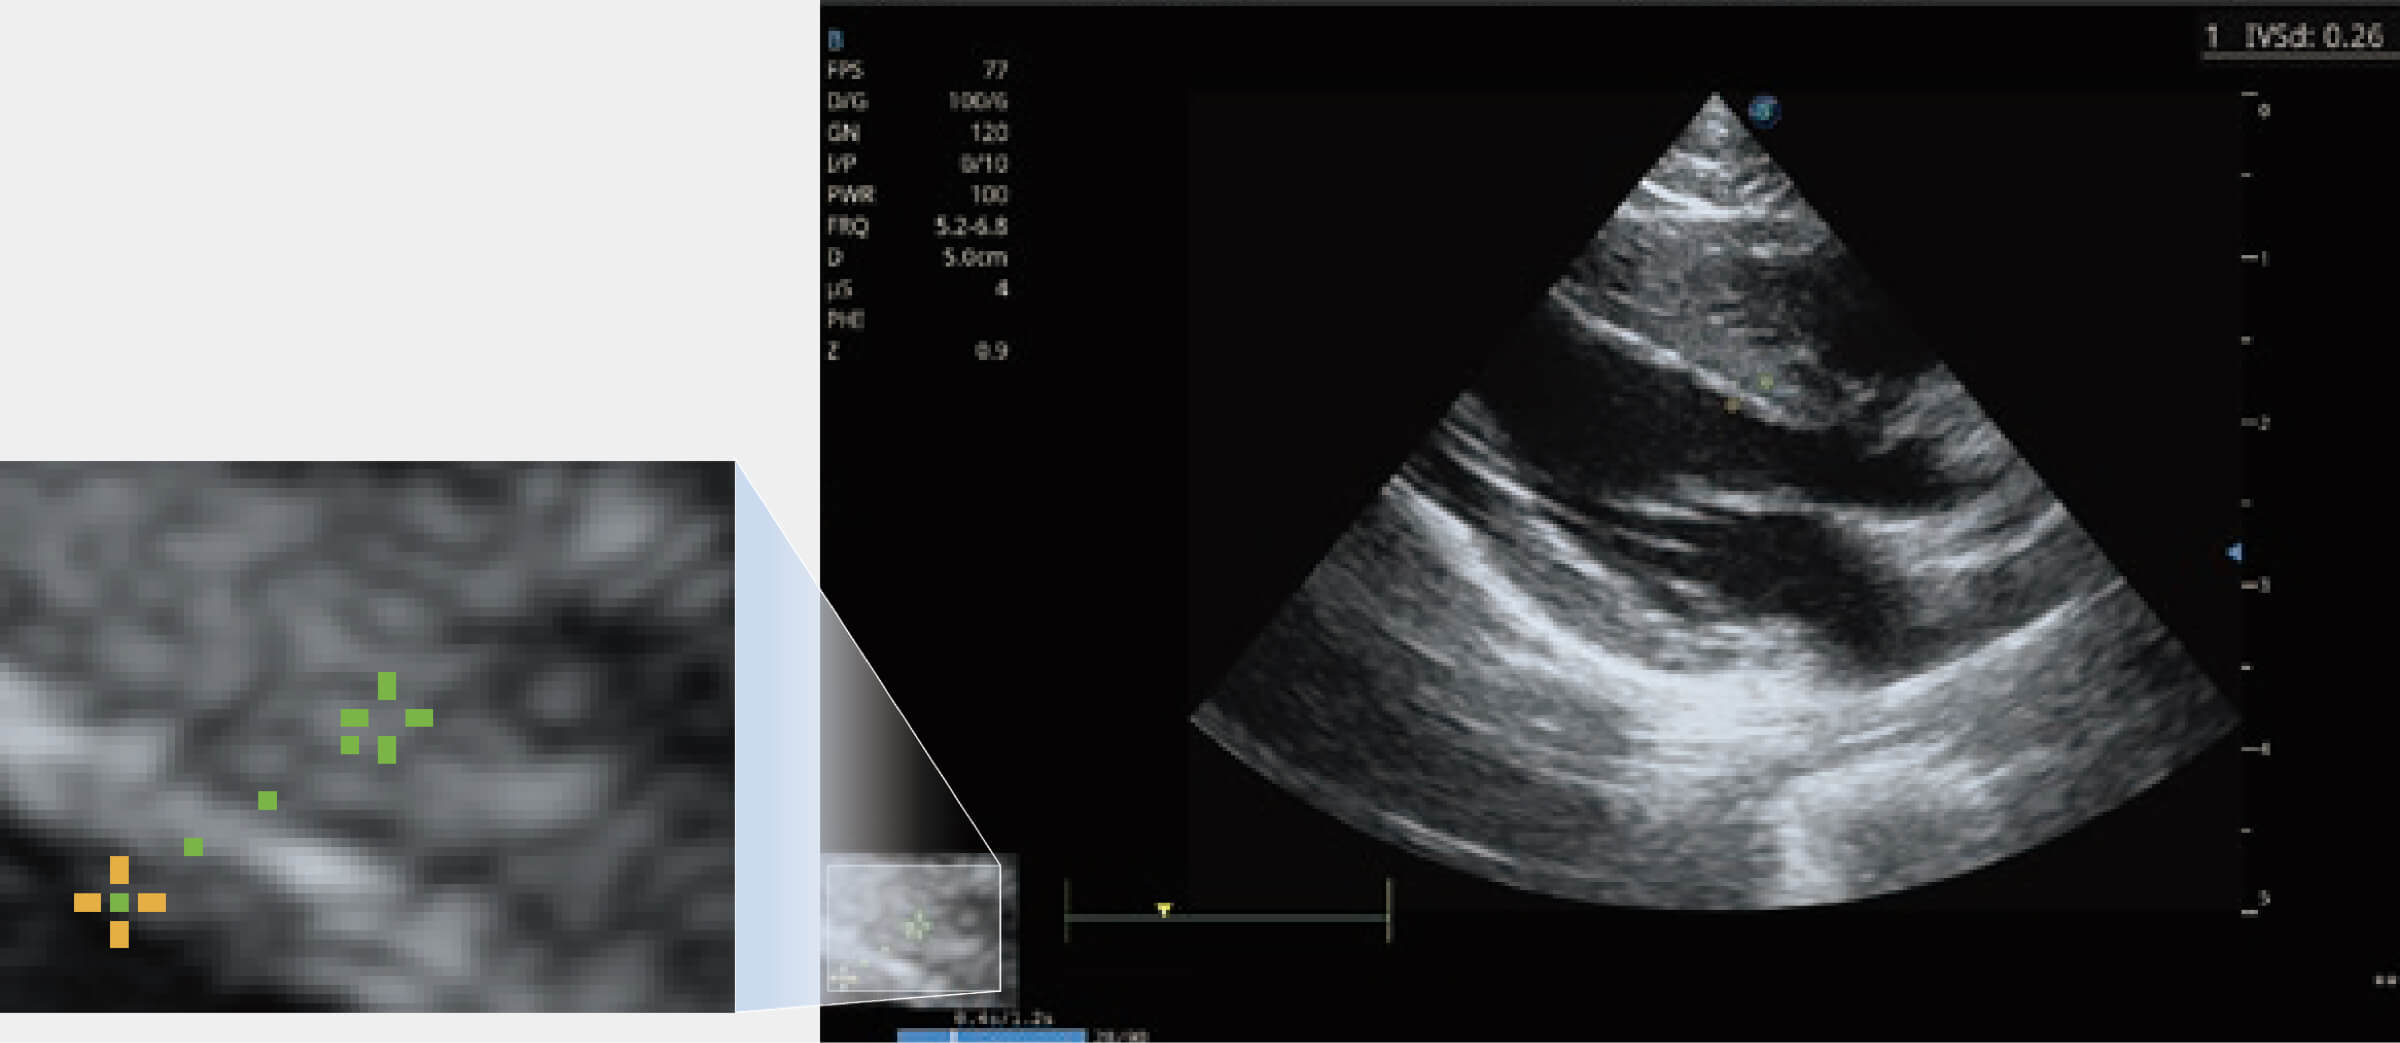

ProPet 80 配備了豐富的心臟探頭群、先進(jìn)的成像技術(shù)和專業(yè)的心臟測(cè)量工具,可幫助動(dòng)物醫(yī)生為不同體型和生理結(jié)構(gòu)的動(dòng)物提供心臟和心肌功能的全面評(píng)估。

通過(guò)360度任意調(diào)節(jié)3條M型取樣線,在同一心動(dòng)周期上觀察心臟不同位置的運(yùn)動(dòng)曲線,得到準(zhǔn)確的心功能測(cè)量數(shù)據(jù),有效評(píng)估心肌運(yùn)動(dòng)及左心室功能。